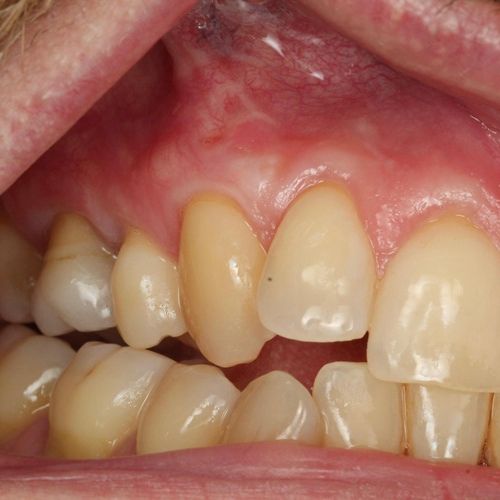

![]() | ![]() |

| Free gingival graft surgery’ to thicken gum and prevent further recession | Gum recession surgery in an aesthetic site |